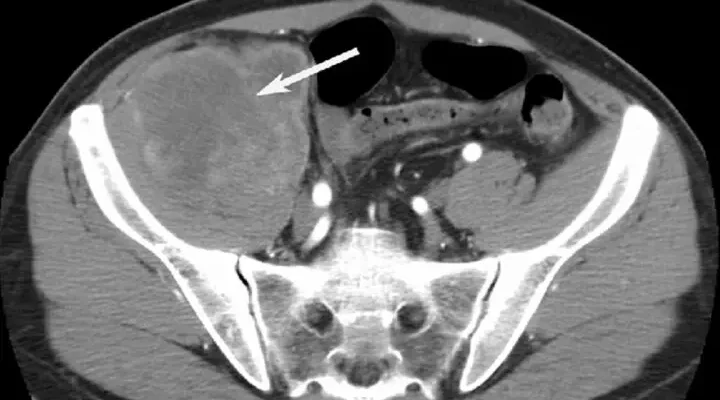

Pelvik MR, çeşitli sağlık sorunlarının teşhisi ve tedavi planlaması için kullanılır. Genellikle, pelvik bölgedeki ağrıların nedenini belirlemek, anormal kitleleri değerlendirmek, kadın üreme organları, mesane, prostat gibi yapılar üzerinde detaylı incelemeler yapmak amacıyla çekilir.

Pelvik MR, birçok ciddi sağlık sorununu teşhis etmede etkili bir yöntemdir. Kadınlarda rahim, yumurtalık ve fallop tüplerindeki kitleler, endometriozis ve fibroidler gibi durumlar tespit edilebilir. Erkeklerde ise prostat hastalıkları ve testis tümörleri gibi rahatsızlıkların teşhisinde kullanılır. Ayrıca, mesane kanseri, bağırsak problemleri, pelvik inflamatuar hastalıklar ve lenf nodu değerlendirmeleri de pelvik MR ile yapılabilir.

Pelvik MR, pelvis bölgesindeki birçok yapının detaylı görüntülerini sunar. Bu sayede, kaslar, bağlar, kemikler, sinirler ve iç organlar hakkında ayrıntılı bilgi elde edilir.